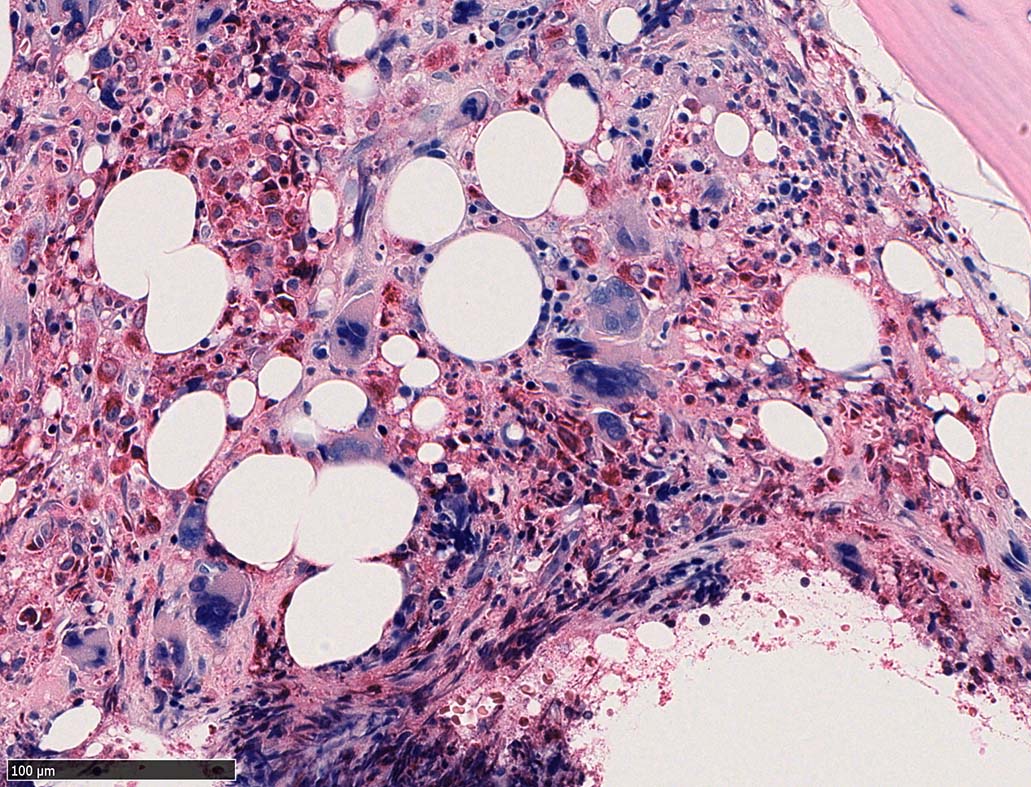

骨髄組織所見 bone marrow biopsy total 6mm in length

塗銀染色

CD42b染色

黒染する弾性線維の増生のほか, 赤く染まる膠原線維の増生が確認される. MF-2 fibrosis. 鍍銀染色の核染色をすると膠原線維の赤染がわからなくなるので行わない.